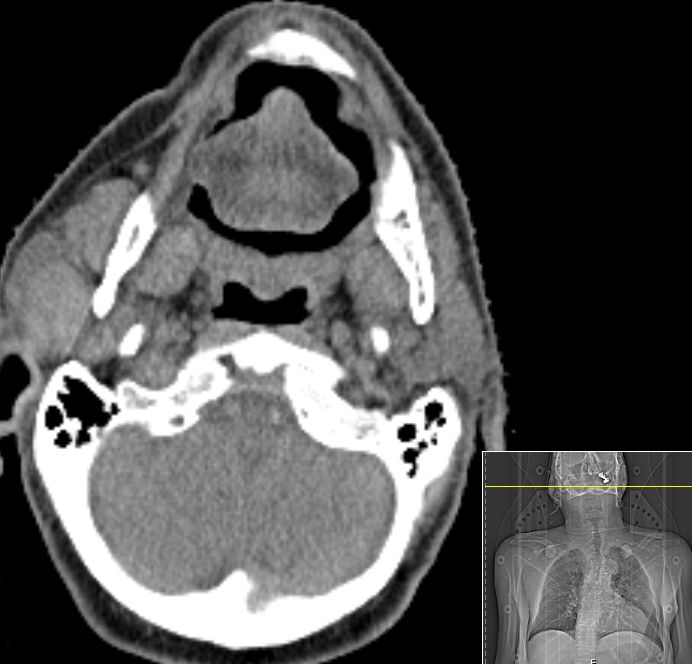

76-jähriger Mann, der vor 9 Monaten ein lymphogen und pulmonal metastasiertes Adenokarzinom der Lunge entwickelte.

Nach Carboplatin/Pemetrexed partielle Remission. Jetzt Progress unter Pemetrexed maintenance. Bei der Bestrahlungsplanung fiel eine metastasenverdächtige Schwellung der rechten Parotis auf.![]() |